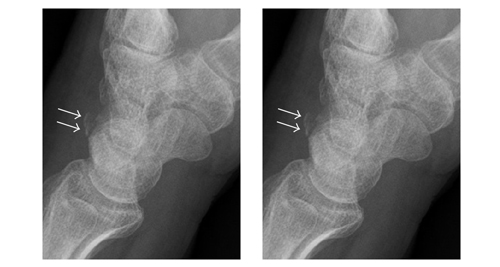

X-rays are the most common imaging method used to confirm a fracture. Lateral (side) views of the coccyx allow doctors to see misalignment or bone fragments. However, small cracks may be hard to detect if swelling obscures the view.